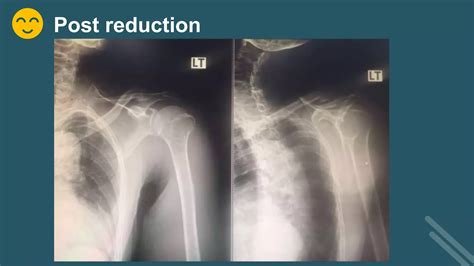

The immediate goal is reduction—the process of guiding the humeral head back into the glenoid socket. This procedure is performed by medical professionals using various techniques, including the Stimson technique, traction-countertraction, or external rotation methods. Once the shoulder is reduced, the primary focus shifts to immobilization and protection.

Diagnostic Procedures and Imaging

X-ray (AP and Scapular Y views) Confirms the direction of dislocation and excludes fractures.